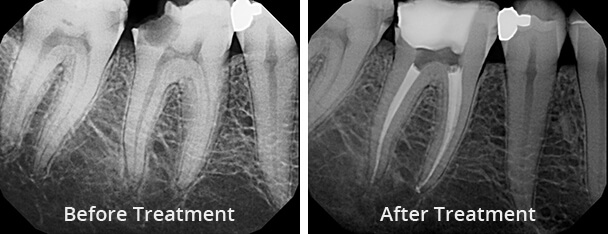

Before your root canal, your dentist will assess your dental health and take X-rays to determine the extent of the infection. It’s common to experience some anxiety about the procedure, but modern dentistry has made root canals much more comfortable than in the past. Your dentist may discuss options for sedation or local anesthesia to ensure a pain-free experience.

Before the procedure, you may experience pain, swelling, or sensitivity in the affected tooth. After the treatment, these symptoms usually subside within a few days, leaving you with a stronger and healthier tooth. Crowns or permanent fillings help restore both the appearance and function of your teeth, giving you confidence in your smile.